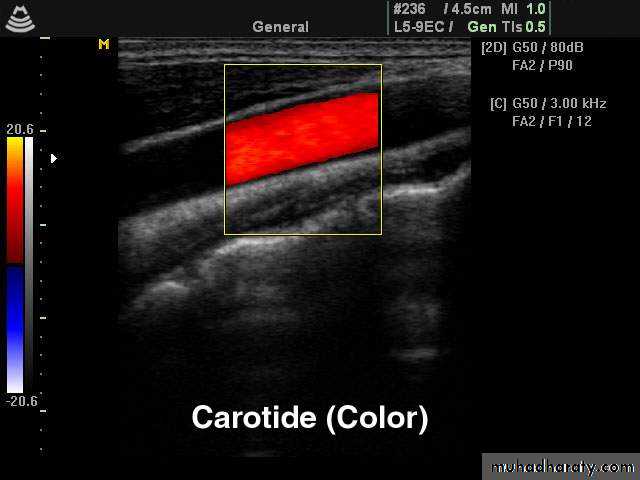

• Patients whose symptoms resolve within 24 hours are referred to as having a transient ischaemic attack (TIA). A common cause for a TIA is embolus from an atheromatous stenosis of the internal carotid artery. The presence of atheromatous plaque and degree of stenosis can be assessed with Doppler ultrasound of the neck. Ultrasound can also demonstrate a dissection of the carotid artery in the neck.